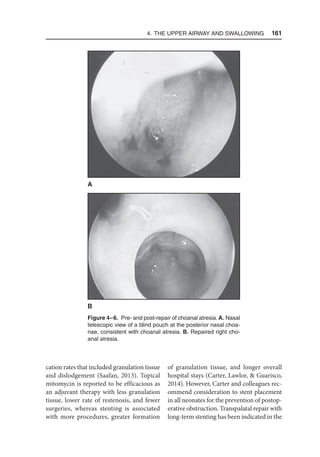

Vagus (X)–SLN Pharynx, larynx, viscera, base of tongue

Note. SLN = superior laryngeal nerve.

2. Anatomy, Embryology, Physiology, and Normal Development  45

in the pharynx and esophagus, even with

esophageal transection or deviation of a

bolus. In contrast, Miller suggested that

peripheral feedback modifies the central

pattern generator as noted by the decrease

in the number of peristaltic waves by devia-

tion of a bolus in the esophagus.